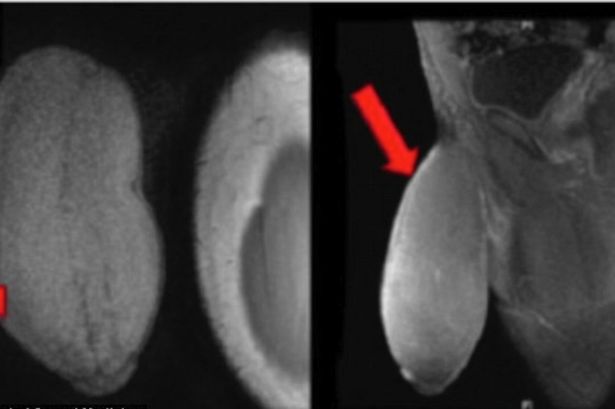

O caso aconteceu na Flórida e foi divulgado pelo renomado Journal of Sexual Medicine. Segundo o artigo publicado no veículo médico, o rapaz possuía um membro de 18 cm em estado flácido, além de uma circunferência de 26 cm – o dito cujo foi descrito como sendo parecido com uma bola de rugby. O adolescente possui 17 anos e teve sua identidade preservada.

O cirurgião responsável pelo procedimento, Rafael Carrion, explicou que o pedido foi feito depois de o adolescente relatar problemas em manter relações sexuais e em praticar esportes. Foram retirados segmentos das laterais do pênis do garoto, em uma operação parecida com a que é feita em outros órgãos – Carrion explica que procurou em toda a literatura médica e não encontrou nada parecido.